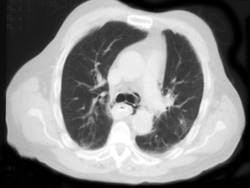

Esophageal Cancer with Celiac Adenopathy